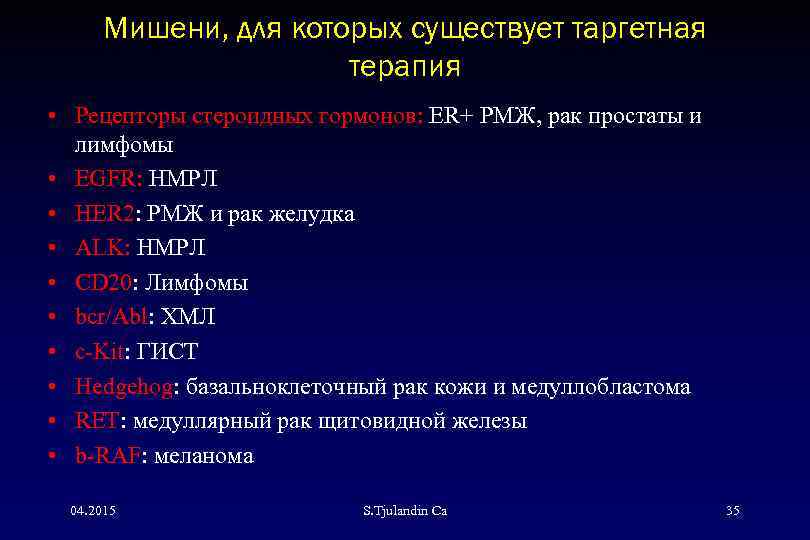

Таргетная терапия РМЖ: Инновации в лечении